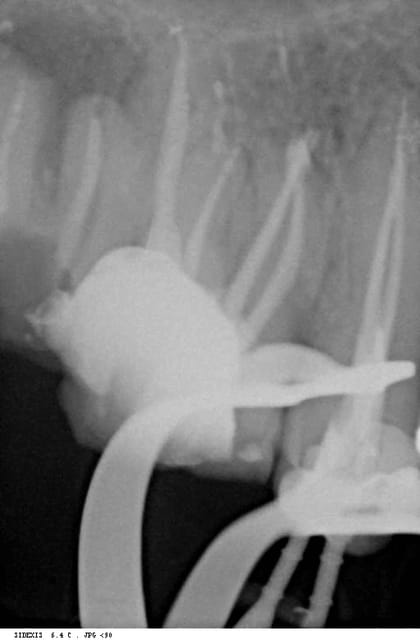

voilà une radio avec une autre incidence: tu vois le canal palatin? tu vois l'obturation dedans? non?

t'as rattrapé la courbure, pour le palatin,c'est flou, il me semble que cette racine a une structure osseuse,mais bon,je vais changer de lunettes!mais on n'est pas mardi matin aujourd'hui?